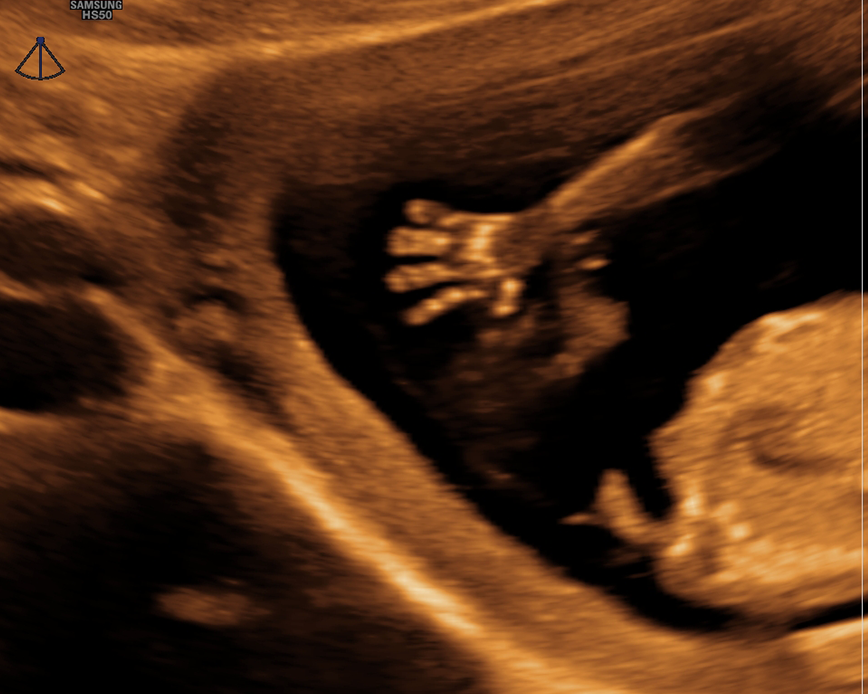

Con nuestra tecnología 5D y 6D de alta resolución, podrás ver la carita, las manos, los pies, la columna y el sexo de tu bebé con imágenes de alta calidad. Además, podrás apreciar los gestos de tu bebé en tiempo real. Esta ecografía también nos ayuda a detectar las malformaciones congénitas que pudiera tener el feto.